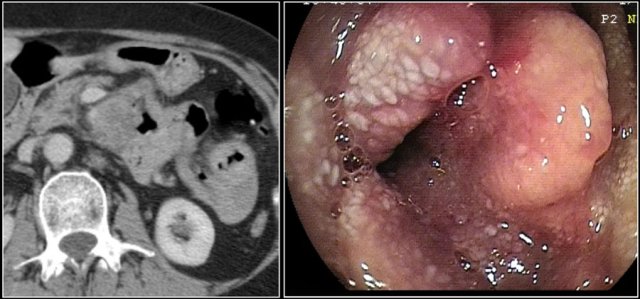

The images show a circumferential mass with shouldering of the margins.

Large adenocarcinomas can mimic a lymphoma as in this case.

The images show an irregular mass in the proximal jejunum.

Although it is a large circumferential growing mass, the lumen is not obstructed.

There is a large conglomerate of hypodense lymph nodes in the adjacent mesentery, consistent with necrotic lumph node metastases (lower image).

This proved to be an adenocarcinoma, but these findings could very well represent a lymphoma.

Here the endoscopic image of the tumor.